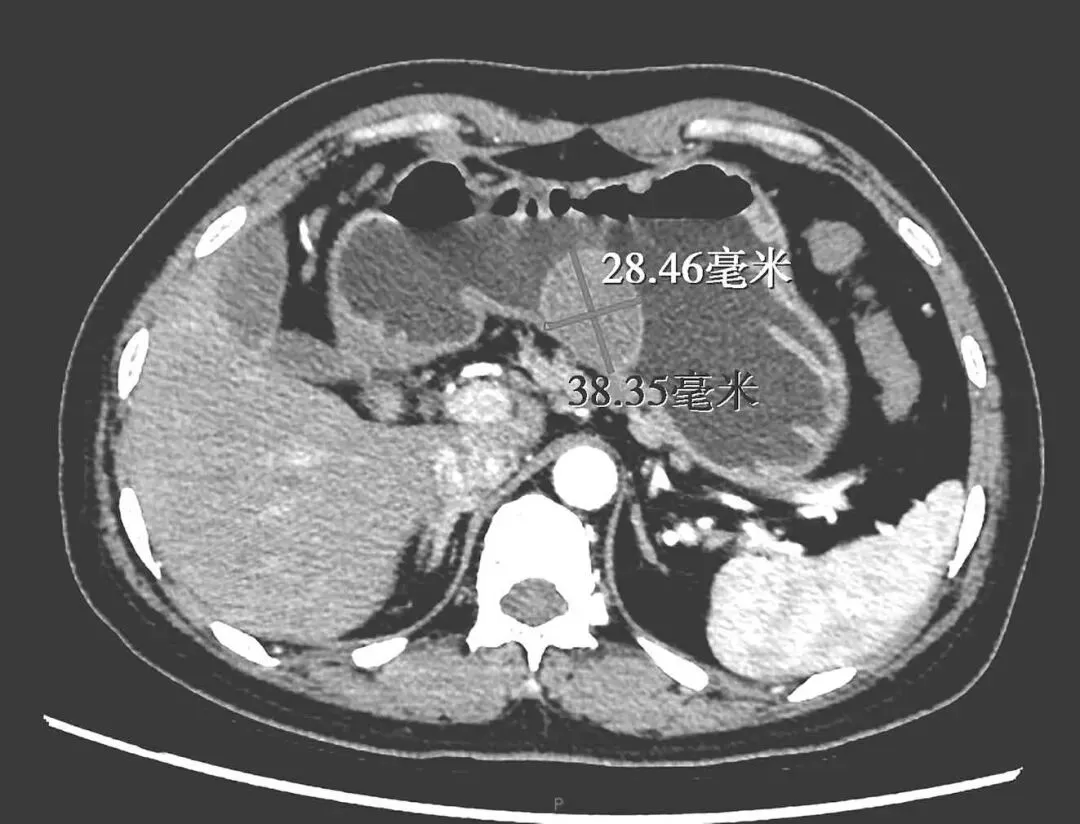

胃增强CT:胃体小弯侧占位,CT表现倾向于黏膜下来源,考虑GIST可能大,建议结合内镜及病理结果。肝脏多发微小囊肿。胆囊腺肌症。扫及两侧胸腔少量积液(图2-2)

2-2 CT提示胃体小弯侧占位